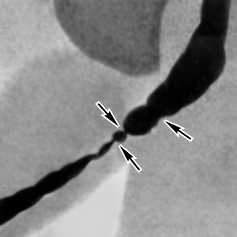

• восходящая и нисходящая уретрография;

• рентгенография с введение в мочеиспускательный канал рентгенпозитивных инструментов.